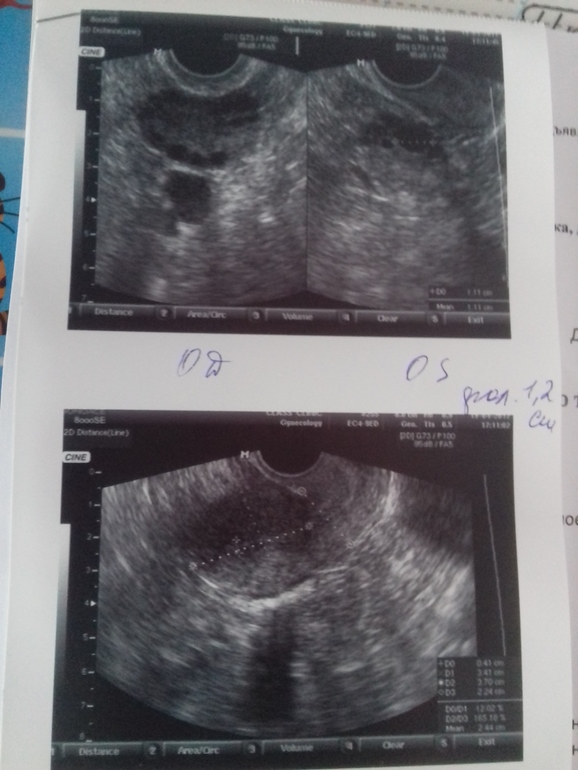

Сегодня 11 д.ц. сходила на узи,а там в ля фоллик 12мм доминирующий. У меня улыбка до ушей,аж до сих пор скулы болят. Но вот эндик 4.1. Врача своего сегодня не застала. Завтра она работает с 12 часов,буду звонить. Какой хотя бы должен быть эндик для зачатия?

Спасибо за ответ. А у меня с 11 д.ц. по 17 д.ц. вырос только с 12 до 16мм и все. Завтра иду на узи 19 д.ц. не знаю чего ожидать. Эндик норм у меня

Я еще на 13 д.ц. пойду. Фоллик то определился доминантный,значит он и должен расти дальше. А как уже достигнет 18-21мм то укол хгч. А вот эндометрий вообщем она сказала до 5мм. Я вот и переживаю за эндик.